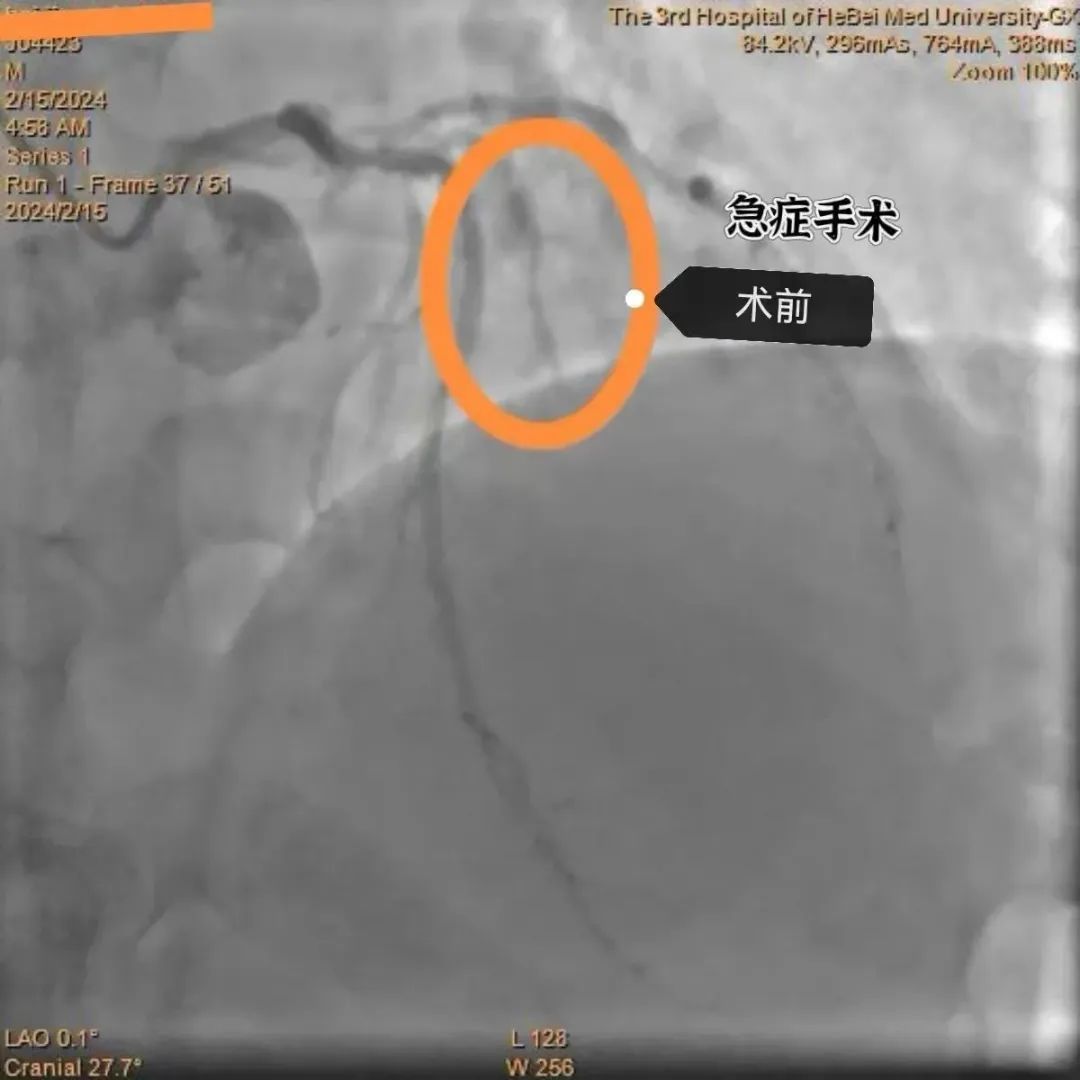

术中冠脉造影结果显示,患者的大对角支近段闭塞,而且开口被曾经放置的支架覆盖,手术难度较大。面对挑战,殷洪山主任凭借丰富的经验和精湛的技术,沉着应对,精准操作,经过一个多小时的努力,顺利开通闭塞血管,患者转危为安。